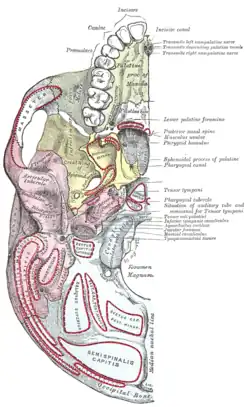

Mouth (oral cavity) Left maxilla, outer surface

Left maxilla, outer surface Base of skull, interior surface

Base of skull, interior surface